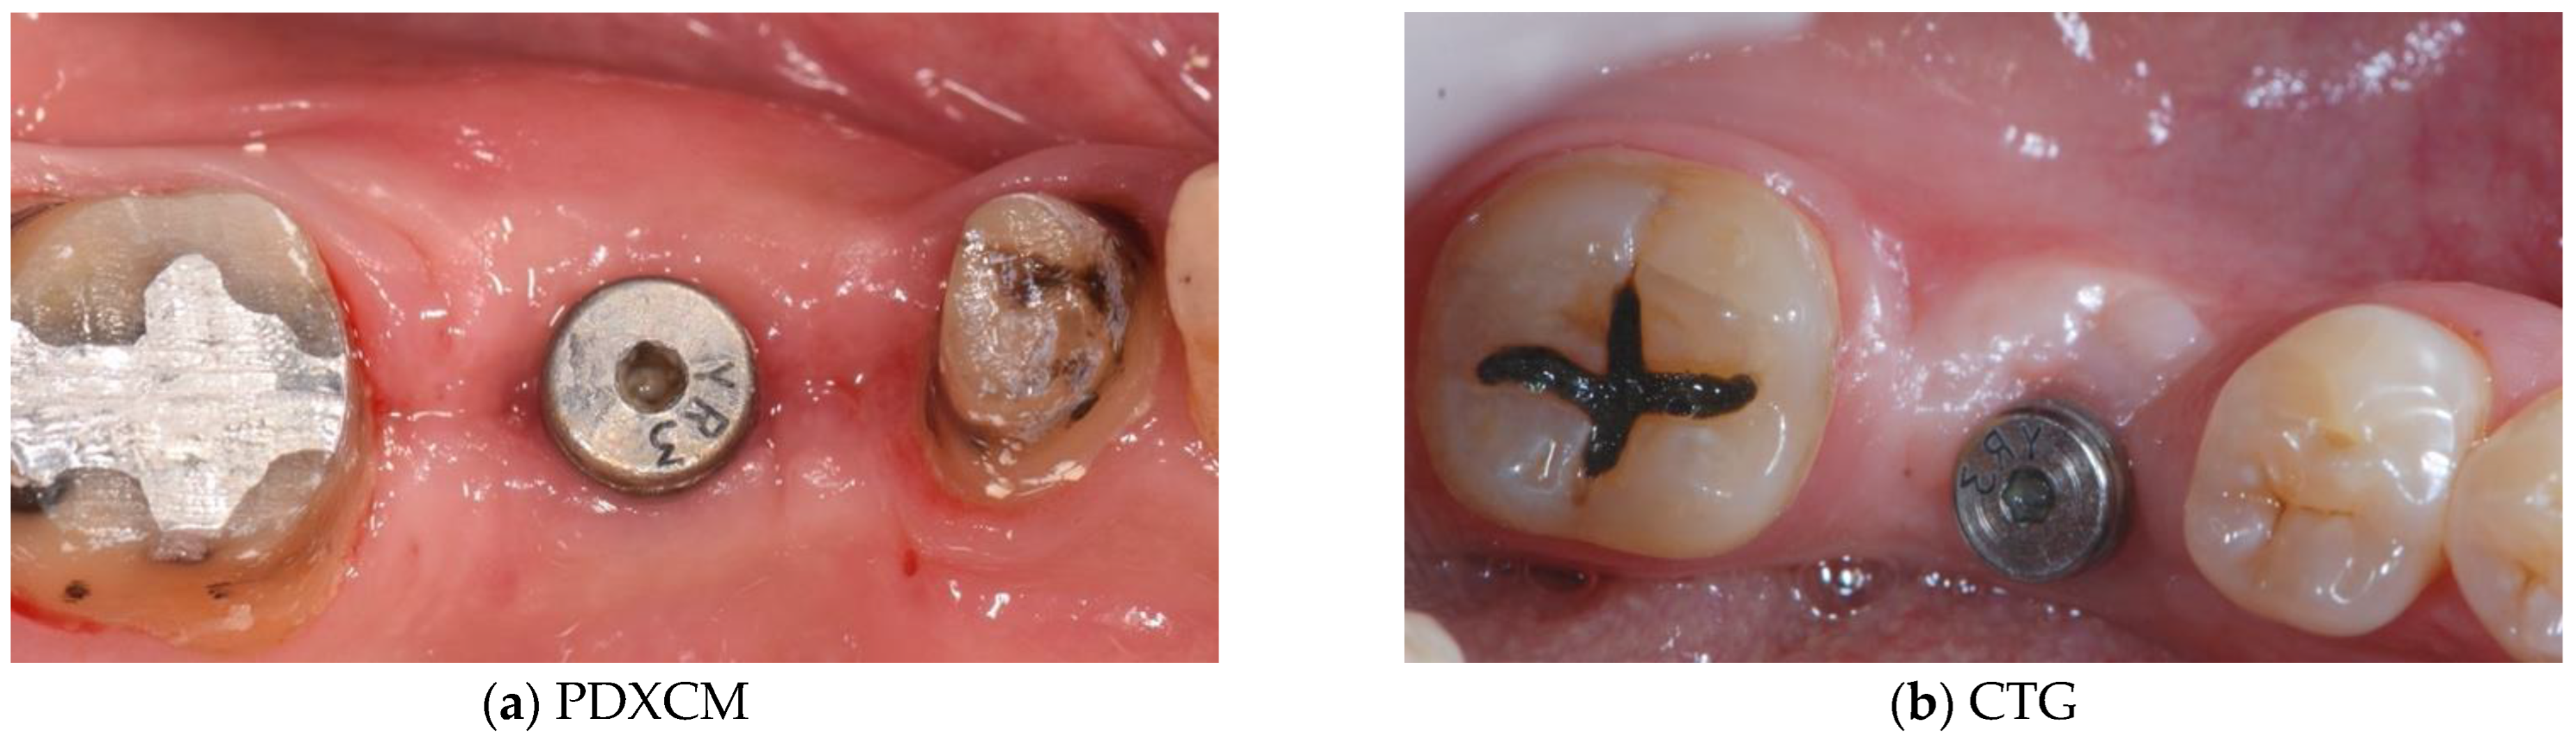

| Papi et al. [27] | 12 patients | Prospective cohort study | 12 months | N R | PDXCM: 1.25 |

| Zafiropoulos et al. [38] | 27 patients | Prospective, randomized examiner-blinded controlled clinical study | 6 months | N R | PDXCM: 1.06 |

| Stefanini et al. [39] | 10 patients | Case series | 12 months | PDXCM 0.65 ± 0.41 | PDXCM: 1.2 ± 0.18 |

| Papi and Pompa 12 [40] | 12 patients | Prospective pilot cohort study | 12 months | PDXCM: 4.32 | N R |

| Schmitt et al. [41] | 14 patients | Controlled clinical trial | 6 months | N R | PDXCM: 0.30 ± 0.16 |

| Verardi et al. [42] | 24 patients 24 implants | Prospective study | 6 months | PDXCM 1.33 ± 0.71 | N R |